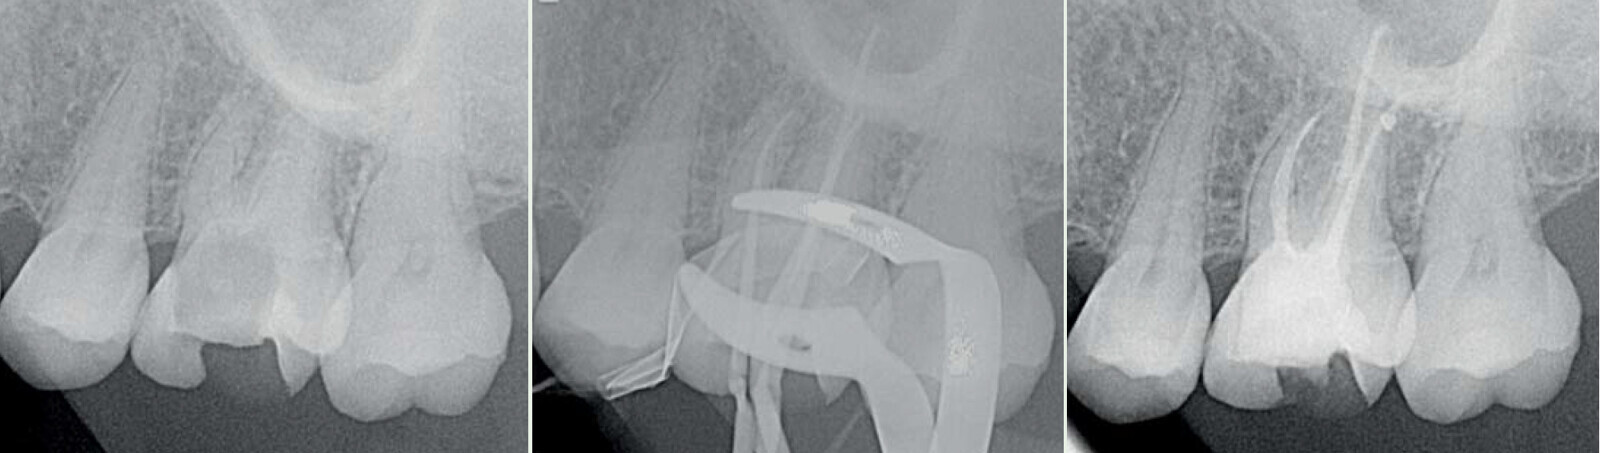

Fig. 10 : Cas clinique Dr Camille Bertrand.

Fig. 11 : Cas clinique Dr Carlos Spironelli.